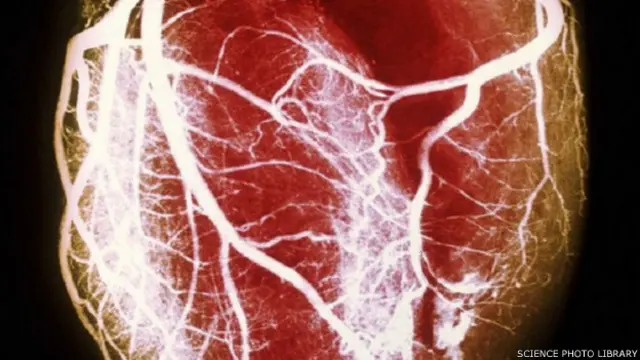

،تصویر کا ذریعہSCIENCE PHOTO LIBRARY

اس مطالعے میں تحقیق کرنے والوں نے دل کی صحت کا تجزیہ کرنے کے لیے طبی سکین کا سہارا لیا۔ انھوں نے اس میں دل کو خون فراہم کرنے والی شریانوں کا بغور مطالعہ کیا۔

دل کی شریانوں کے متعلق بیماری میں عام طور پر رفتہ رفتہ رگ و ریشے پر چربی چھانے لگتی ہے اور اس سے خون کی فراہمی متاثر ہوتی ہے۔

سکین میں محققوں نے دل کے قریب کی شریانوں کی دیواروں پر کیلشیم کے معمولی سے بھی جمنے کا مطالعہ کیا تاکہ بیماری کے ابتدائی رجحان کی نشاندہی کی جا سکے۔